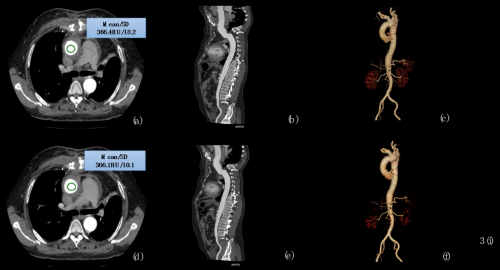

2018年2月,基于NeuViz 128 精睿 CT的AI成像优化技术,双方携手对NeuViz 128 精睿 CT行主动脉 CTA 检查的 60 例患者,进行常规组和“双低组”(低辐射剂量、低对比剂用量)的研究。历时 3 个月的研究,项目成果证明:

在主动脉“双低”扫描的情况下,基于人工智能的图像优化能够有效降低噪声、提高 SNR 和CNR ,明显改善主动脉 CTA 的整体图像质量;与常规扫描辐射剂量与对比剂用量相比,辐射剂量降低约 79.18% ,对比剂用量降低约 50%。

▲通过 AI 优化,“双低”扫描的图像质量得到显著提升

《Application of Artificial Intelligencebased Image Optimization for Computed Tomography Angiography of the Aorta With Low Tube Voltage and Reduced Contrast Medium Volume》课题论文见刊于《Journal of Thoracic Imaging》杂志(胸部及心脏成像技术领域极具影响力的期刊,目前SCI影响因子2.078,深受国内外学术专家们的认可)。